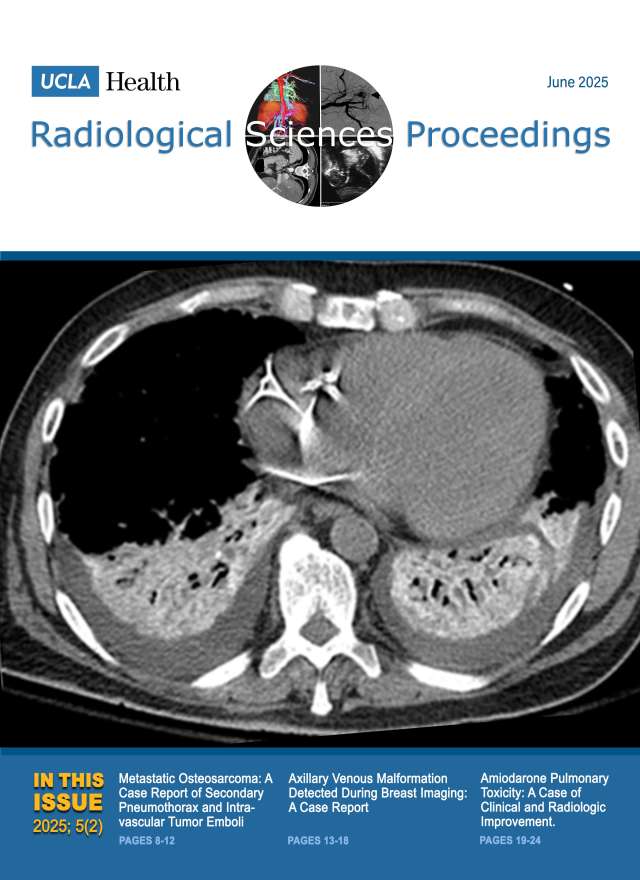

August 2024

Volume 4, Issue 3

- Differentiating Hemangioma and Secondary Angiosarcoma of the Breast: Two Case Reports

- Intraperitoneal Focal Fat Infarction of the Falciform Ligament: A Report of Two Cases

- Tilted Disc Syndrome with Bitemporal Hemianopia in a 67-Year-Old Woman with High Myopia and Mixed/Combined-Mechanism Glaucoma: A Report of a Rare Case